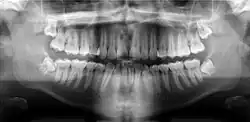

Panoramic radiograph

A panoramic radiograph is a panoramic scanning dental X-ray of the upper and lower jaw. It shows a two-dimensional view of a half-circle from ear to ear. Panoramic radiography is a form of focal plane tomography; thus, images of multiple planes are taken to make up the composite panoramic image, where the maxilla and mandible are in the focal trough and the structures that are superficial and deep to the trough are blurred.

Orthopantomograms (OPTs) are used by health care professionals to provide information on:

- Impacted wisdom teeth diagnosis and treatment planning - the most common use is to determine the status of wisdom teeth and trauma to the jaws.